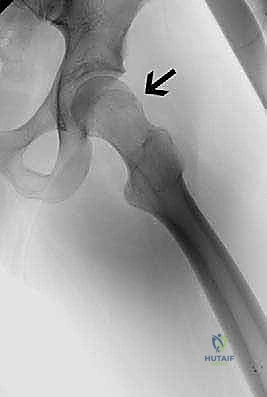

كلمة "Cam" تعني الحدبة. في هذا النوع، يكون التشوه في رأس وعنق عظم الفخذ. بدلاً من أن يكون رأس الفخذ كروياً تماماً وينحدر بسلاسة نحو العنق، تتكون زائدة عظمية (حدبة) عند نقطة التقاء الرأس بالعنق.

عندما يتم ثني الورك، لا يمكن لهذه الحدبة العظمية الانزلاق بسلاسة داخل التجويف الحقي، بل تنحشر بقوة ضد حافة التجويف، مما يؤدي إلى طحن الغضروف المفصلي وتمزيق الشفا الحقي من الأسفل إلى الأعلى. هذا النوع أكثر شيوعاً لدى الشباب الذكور والرياضيين.

* الأشعة السينية العادية (X-Rays): يتم أخذ صور بوضعيات خاصة (مثل وضعية Dunn View) لرؤية مفصل الورك من زوايا متعددة. تكشف الأشعة السينية بوضوح عن وجود حدبة "كام" أو بروز "كماشة"، وتظهر مدى ضيق المسافة المفصلية (مؤشر على الخشونة).